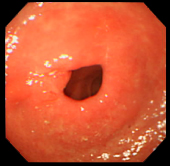

| 症例(胃ポリープ切除1) | |||

| ポリープ | 根元に生理食塩水を注入して水ぶくれ状態をつくり、膨らんだその部分に スネアをかけて高周波の電流を流し病変部を焼き切っている状態。 |